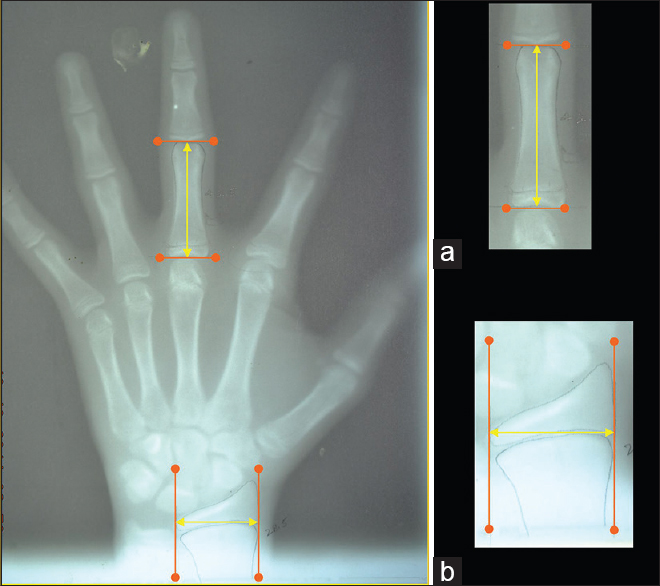

Evaluation of relationship of hand wrist radiograph, cervical vertebral maturation with mandibular growth as skeletal maturity indicators in children

To study the correlation between mandibular growth variables using linear measurements of ramus, body of the mandible and total mandibular length with skeletal maturity indicators such as hand wrist radiographs and cervical vertebral maturation.

Materials and Methods:

A total of 315 patient-records (lateral cephalograms and hand-wrist radiographs) in the age group of 10-13 years were involved. The cephalometric measurements, representative of the mandibular growth, Condylion-Gonion (Co-Go), Condylion-Gnathion (Co-Gn), Gonion-Gnathion (Go-Gn), and posterior-most point of the mandibular condyle-pogonion (Fg-Pg) were traced (McNamara method). The correlation of mandibular growth variables with hand wrist parameters and cervical vertebrae maturation were assessed separately in male and female. Pearson's correlation was used for analysis (Statistical Package for Social Sciences version 17).

Results:

Only 80 subjects were included in final analysis. A highly significant correlation was found among hand wrist parameters, and mandibular growth variables (

P

< 0.001) in both genders. Among males, there was a highly significant correlation between cervical vertebral maturation and mandibular growth variables (

< 0.001), whereas Co-Go has a significant correlation with C2Conc, C3Conc, and C4Conc (

< 0.05). In females, Co-Gn, Co-Go, Go-Gn, and Fg-Pg were significantly correlated with C3Conc and C4Conc (

< 0.001).

Conclusion:

Both the cervical vertebral maturation and mandibular growth variables can be accessed on the lateral ephalogram itself for the evaluation of the skeletal maturity, as effective as a hand wrist radiograph in males and females.